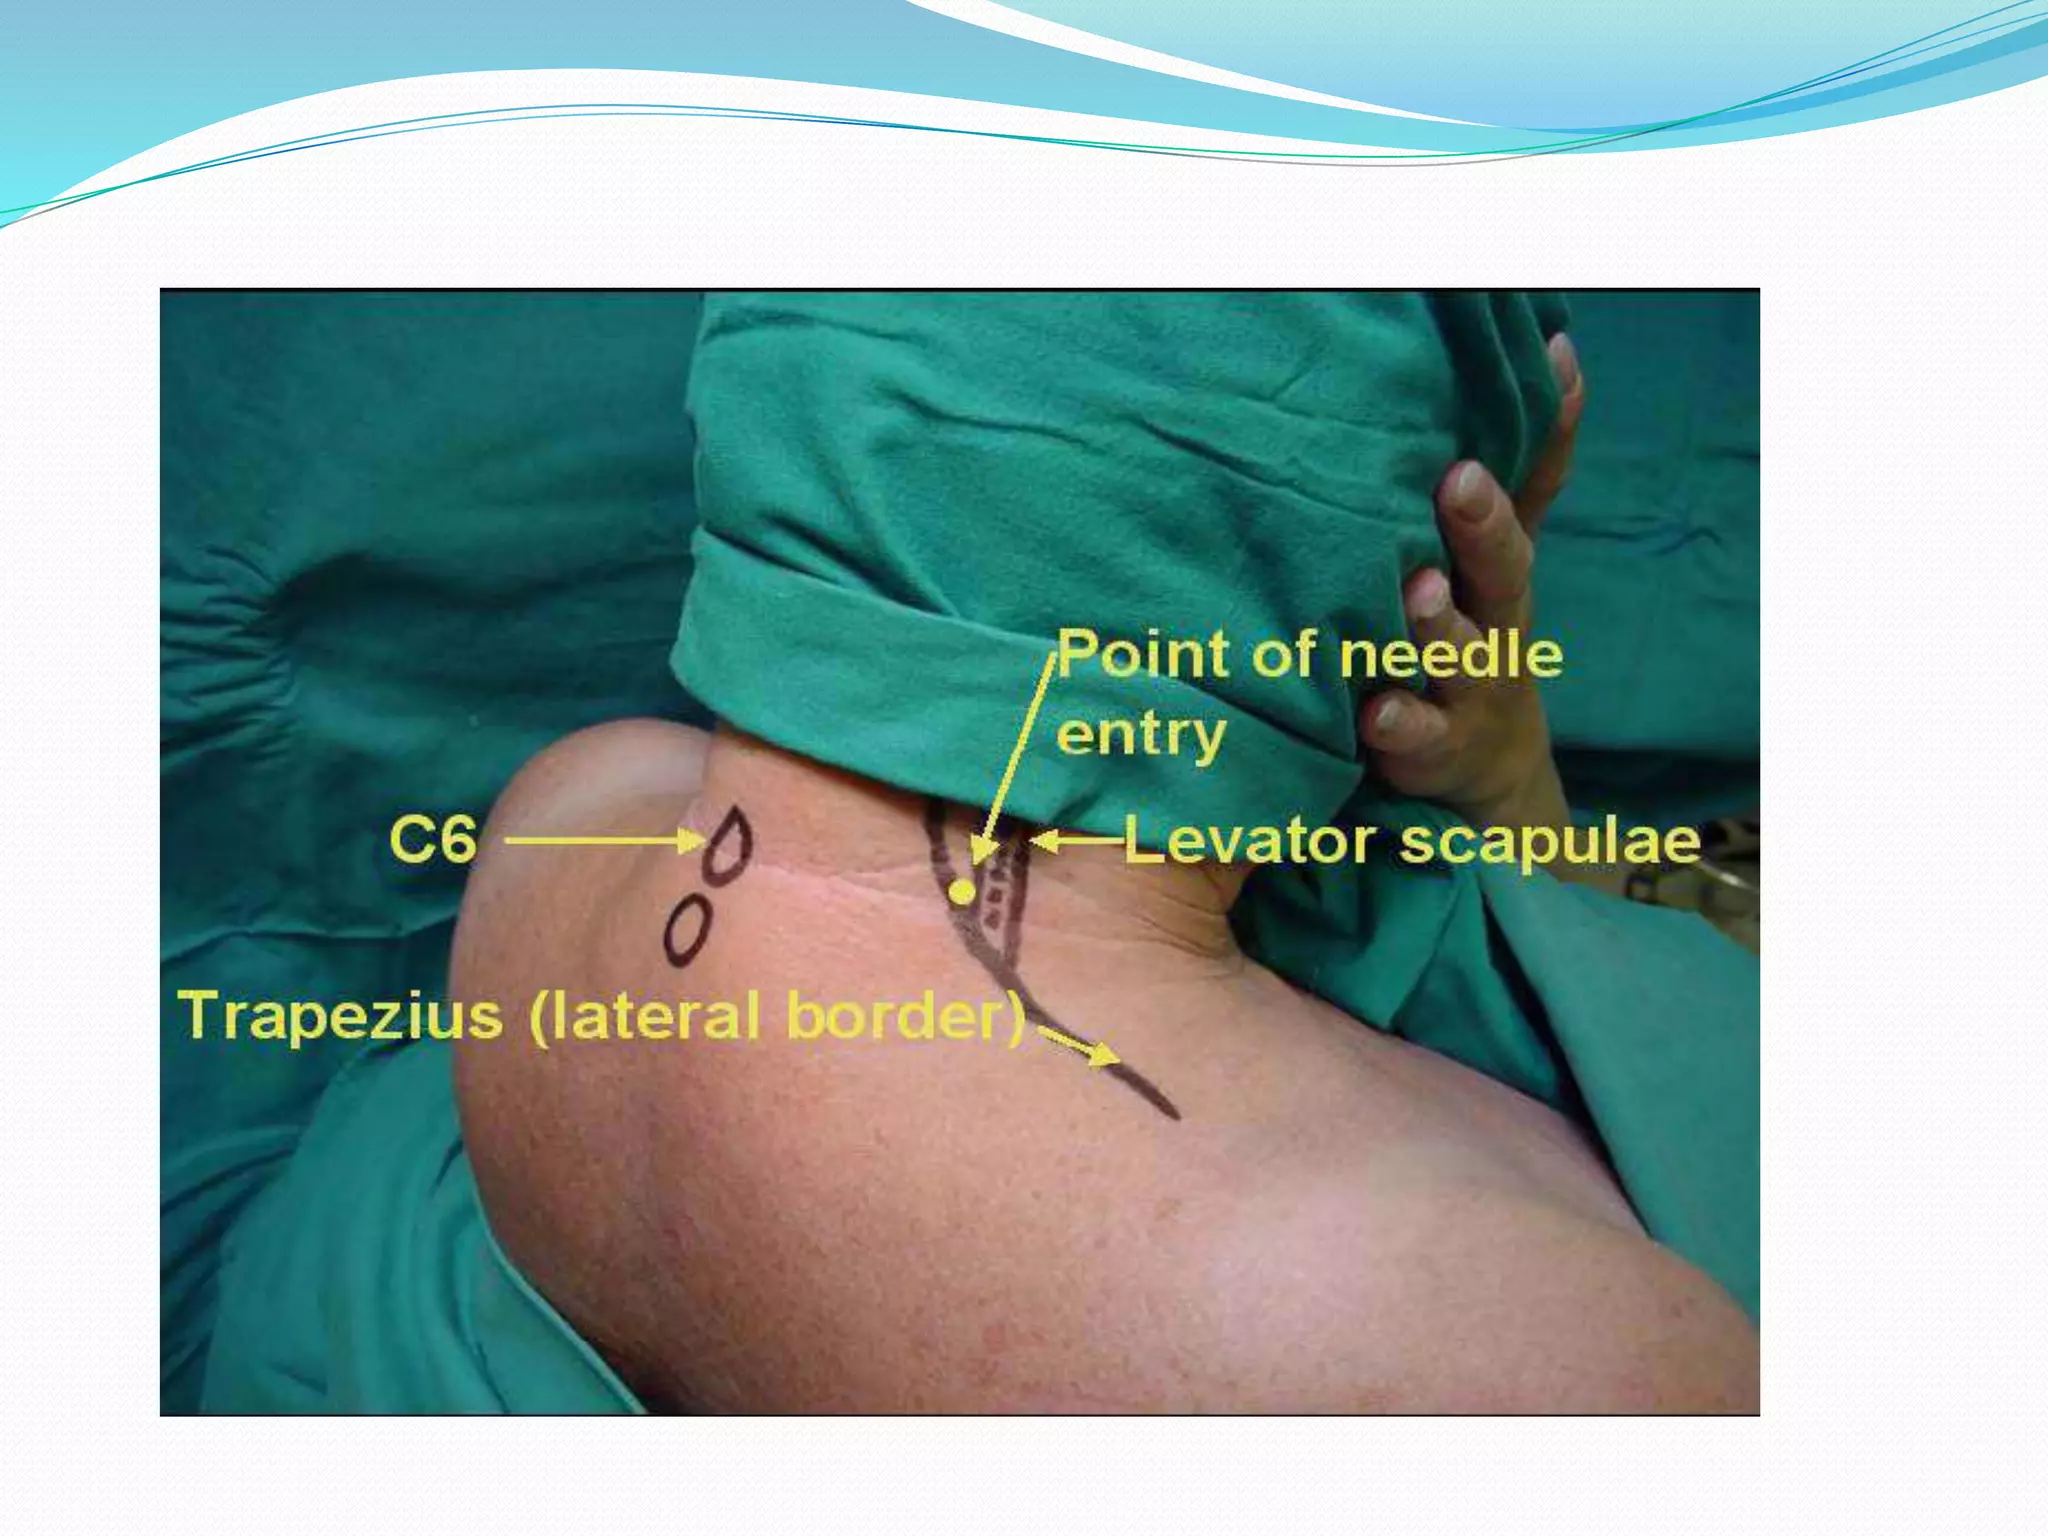

This document provides an overview of brachial plexus anatomy and techniques for brachial plexus nerve blocks. It begins with a description of the brachial plexus formation from cervical and thoracic nerve roots and its branching pattern. Four main approaches for brachial plexus nerve blocks are described: interscalene, supraclavicular, infraclavicular, and axillary. Details are provided on the anatomy and techniques for performing interscalene and supraclavicular brachial plexus blocks. Ultrasound guidance is discussed as an advancement which allows real-time visualization of needle and nerve. Complications are also summarized.